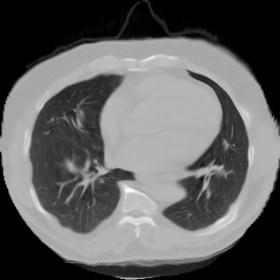

7.3. Real CT images

We now consider applying the proposed image registration method on real lung CT images retrieved from the National Lung Screening Trial (NLST) dataset [1]. Fig. 9(a) and Fig. 9(b) show two slices of lung CT images that we use as the source and the target (see Fig. 9(c) for the absolute intensity difference). We remark that the CT images are originally with different intensity, and so we apply an intensity histogram matching before running the registration experiment. Fig. 9(d) shows the registration result obtained by our proposed method. It can be observed that our method successfully produces a large deformation on the right lung of the source image to match that of the target image (see also Fig. 9(e) for the final absolute intensity difference). On the contrary, DDemons [47] (Fig. 9(f)), LDDMM [5] (Fig. 9(g)), Elastix [29] (Fig. 9(h)) and DROP [18] (Fig. 9(i)) all fail to produce an accurate and bijective registration result. This shows that our method is more capable of handling large deformation image registration.